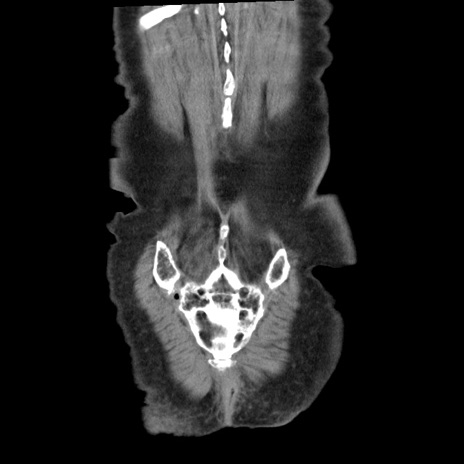

矢状断像

【症例】80歳代女性

【主訴】腹痛

【現病歴】8時間前から腹痛あり来院。

【既往歴】糖尿病、脂質異常症、子宮体癌にて子宮全摘術

【身体所見】意識清明・会話良好だが腹痛で苦悶様、全腹部にわたって反跳痛と圧痛あり

【データ】WBC 13600、CRP 0.14、LDH 224、CK 90